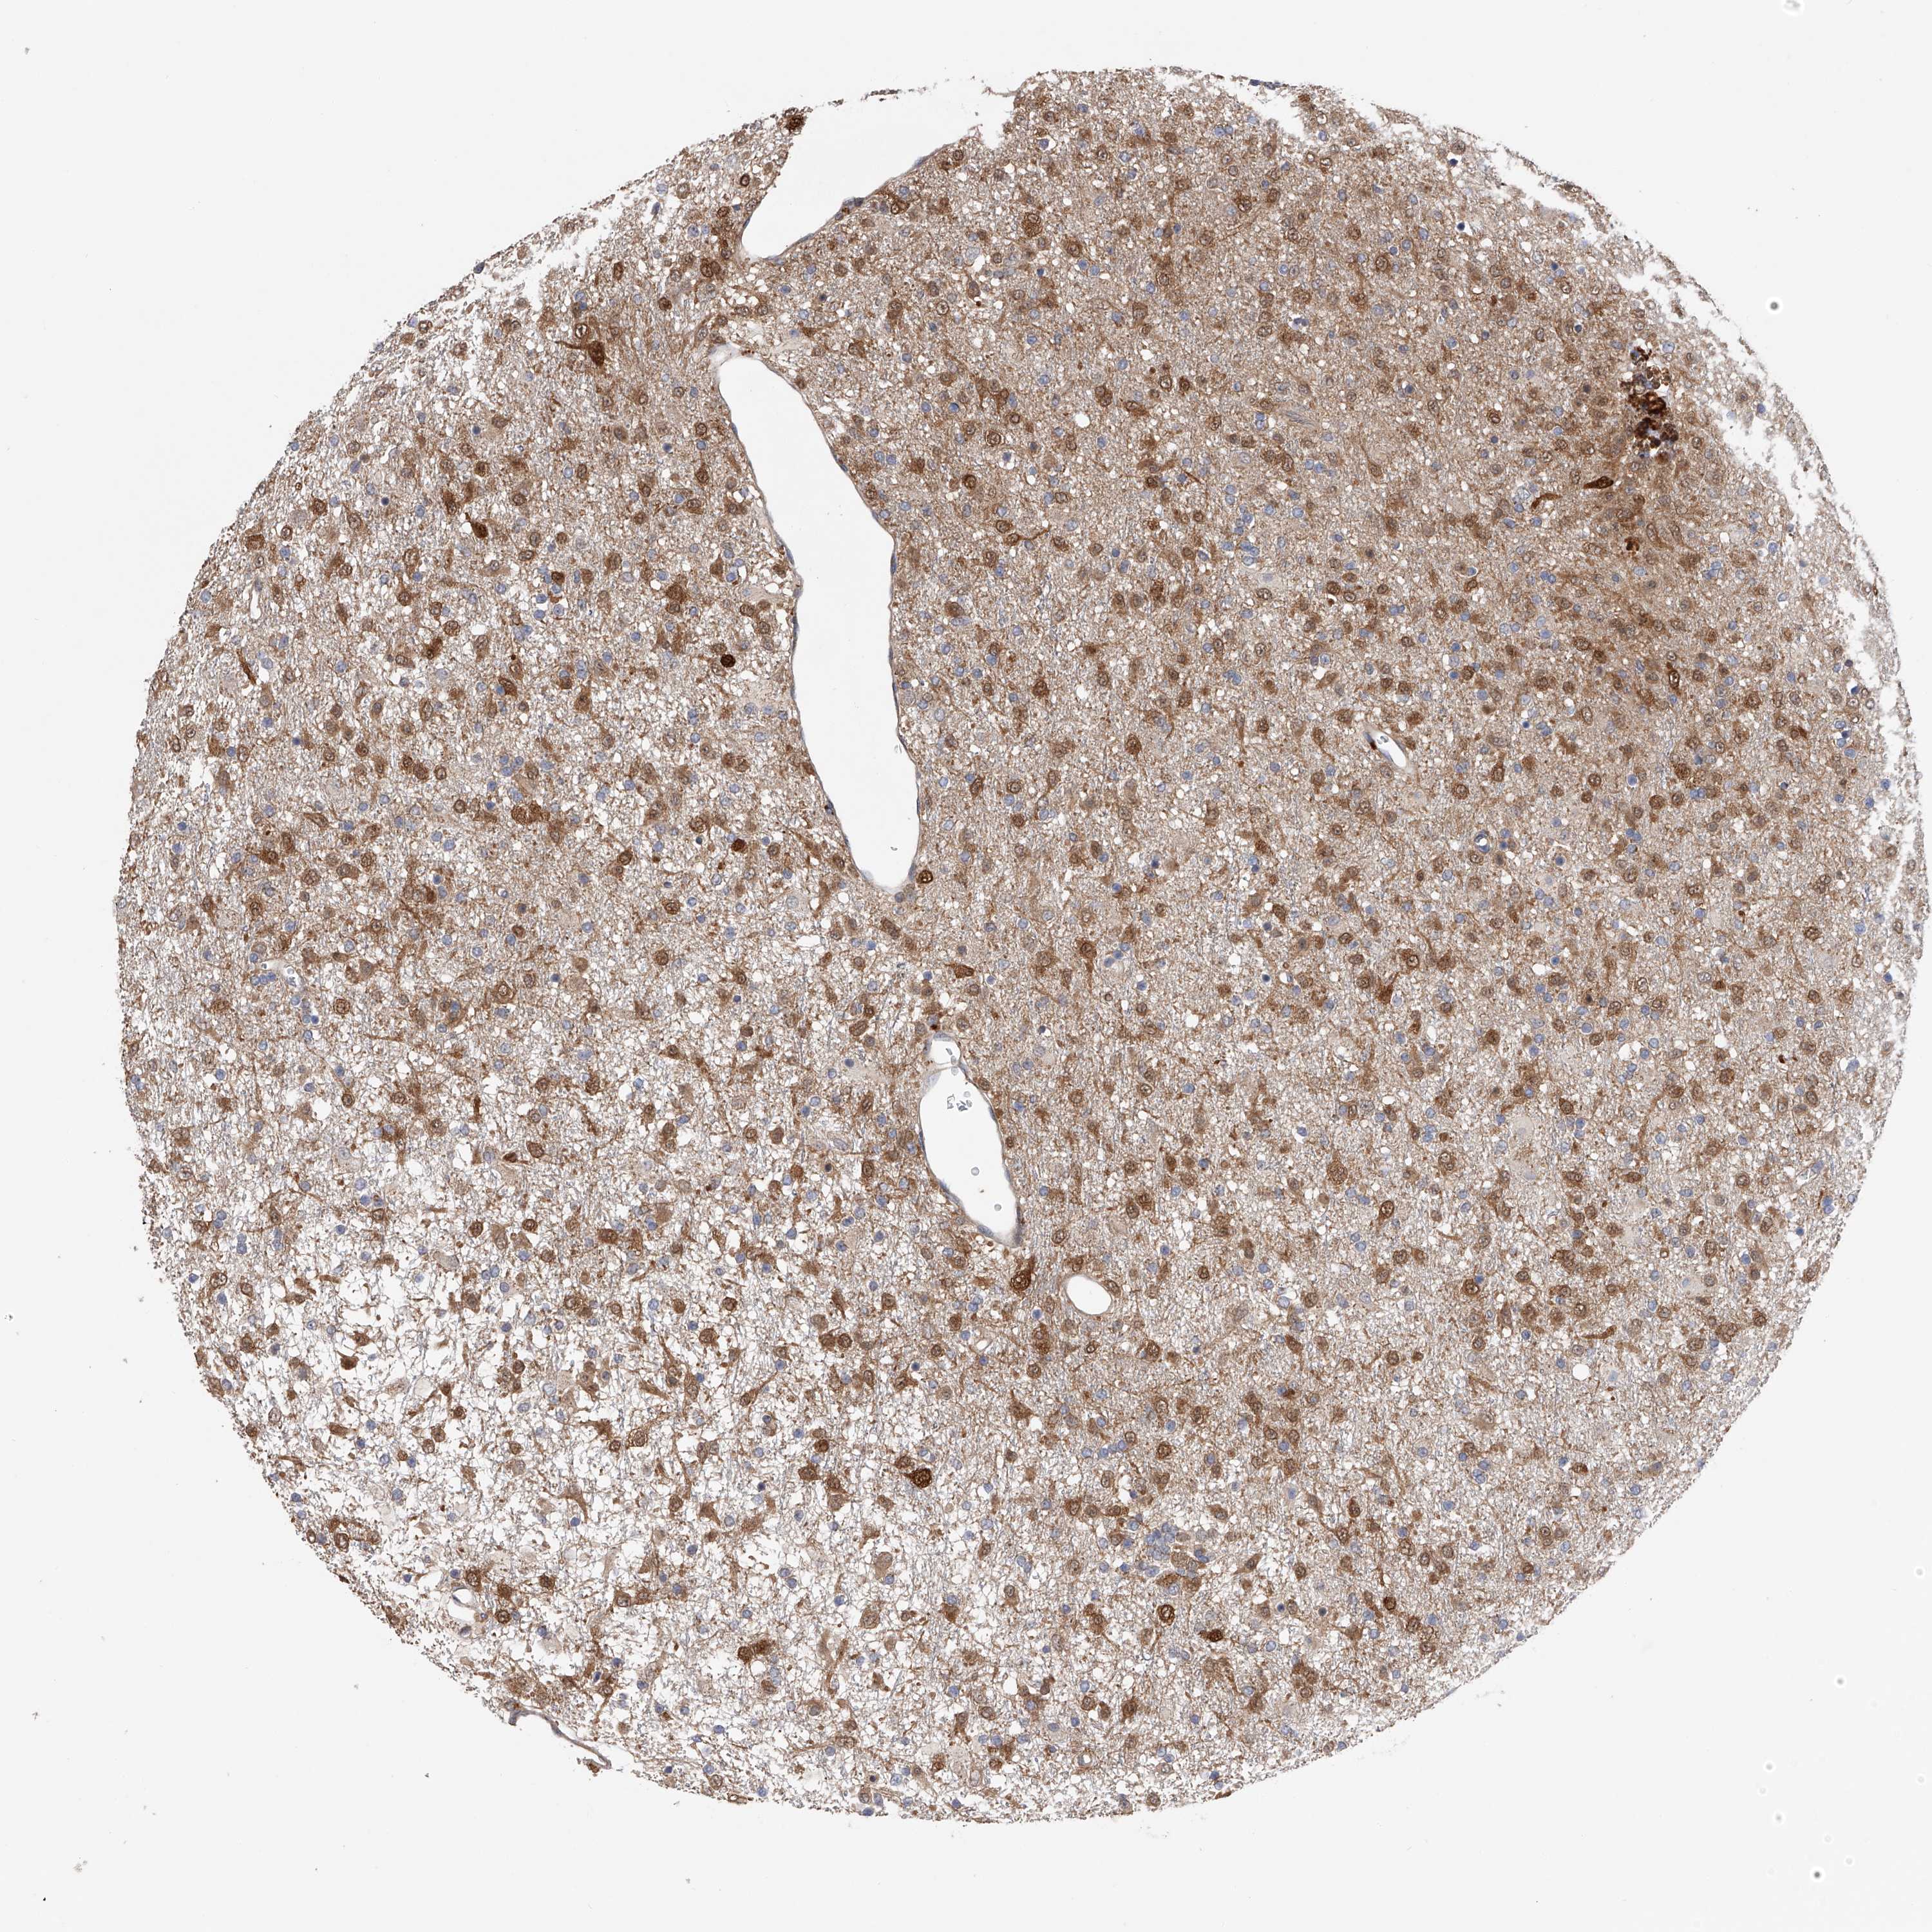

GLIOMA - Protein expressioni

A mouse-over function shows sample information and annotation data. Click on an image to view it in a full screen mode. Samples can be filtered based on level of antibody staining by selecting one or several of the following categories: high, medium, low and not detected. The assay and annotation is described here.

Note that samples used for immunohistochemistry by the Human Protein Atlas do not correspond to samples in the TCGA dataset.

Antibody stainingi

Antibody staining in the annotated cell types in the current human tissue is reported as not detected, low, medium, or high, based on conventional immunohistochemistry profiling in selected tissues. This score is based on the combination of the staining intensity and fraction of stained cells.

Each image is clickable and will lead to virtual microscopy that enables deeper exploration of all samples and also displays staining intensity scores, fraction scores and subcellular localization as well as patient and tissue information for each sample.

Antibody HPA018453

Antibody HPA019055

Antibody HPA028849

Antibody CAB034170

Glioma, malignant, High grade

Glioma, malignant, Low grade

Glioblastoma, NOS